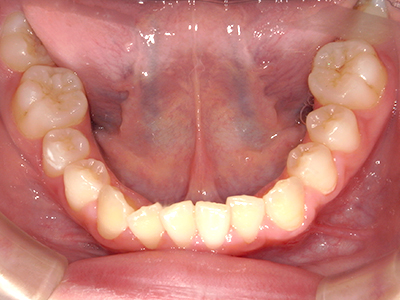

ないき歯科クリニックでは、これからあごが成長していくお子様や、歯並びが気になる成人の方など、さまざまな年代の方に対して矯正治療を行っています。

歯並びやかみ合わせを正しく整えると、笑顔や発音の自信につながり、むし歯・歯周病・口臭の予防にも役立ちます。

【4】矯正治療

矯正装置を装着し、調整しながら少しずつ歯を移動させ、歯並びを整えていきます。